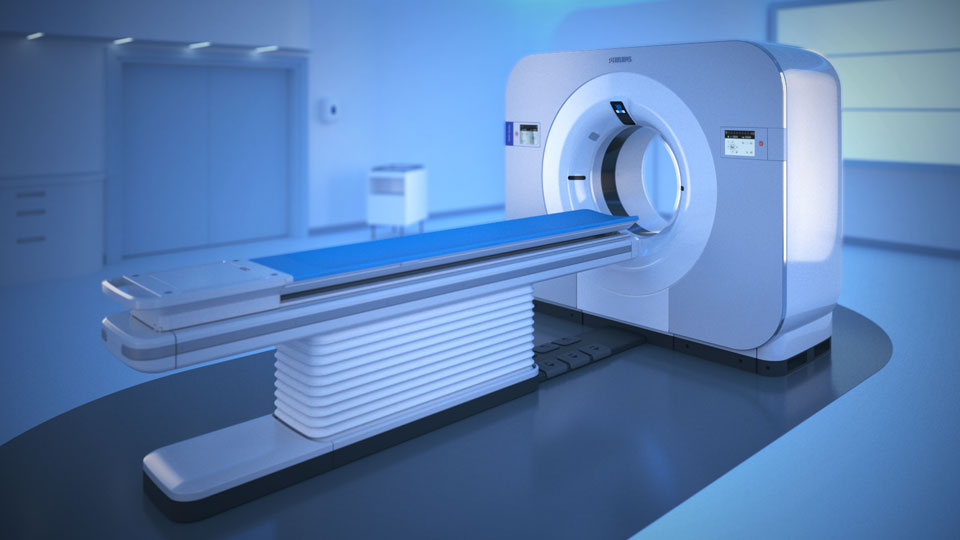

Zero compromise

With detector-based spectral, you acquire multiple layers of data—conventional and spectral—within a single exposure and without special scan modes for improved tissue characterization and visualization.

Scan as usual A single scan for fast, low-dose conventional and spectral data for every patient, every time.

It’s not just CT.

It’s spectral results without compromise.

Experience the simplicity of spectral-detector CT.